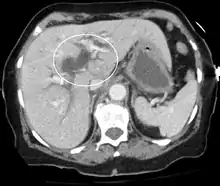

Biliary-tract dilation due to obstruction as seen on CT scan (axial plane)

Most people presenting with jaundice have various predictable patterns of liver panel abnormalities, though significant variation does exist. The typical liver panel includes blood levels of enzymes found primarily from the liver, such as the aminotransferases (ALT, AST), and alkaline phosphatase (ALP); bilirubin (which causes the jaundice); and protein levels, specifically, total protein and albumin. Other primary lab tests for liver function include gamma glutamyl transpeptidase (GGT) and prothrombin time (PT).[36] No single test can differentiate between various classifications of jaundice. A combination of liver function tests and other physical examination findings is essential to arrive at a diagnosis.[37]

Medical imaging such as ultrasound, CT scan, and HIDA scan are useful for detecting bile-duct blockage.[40]